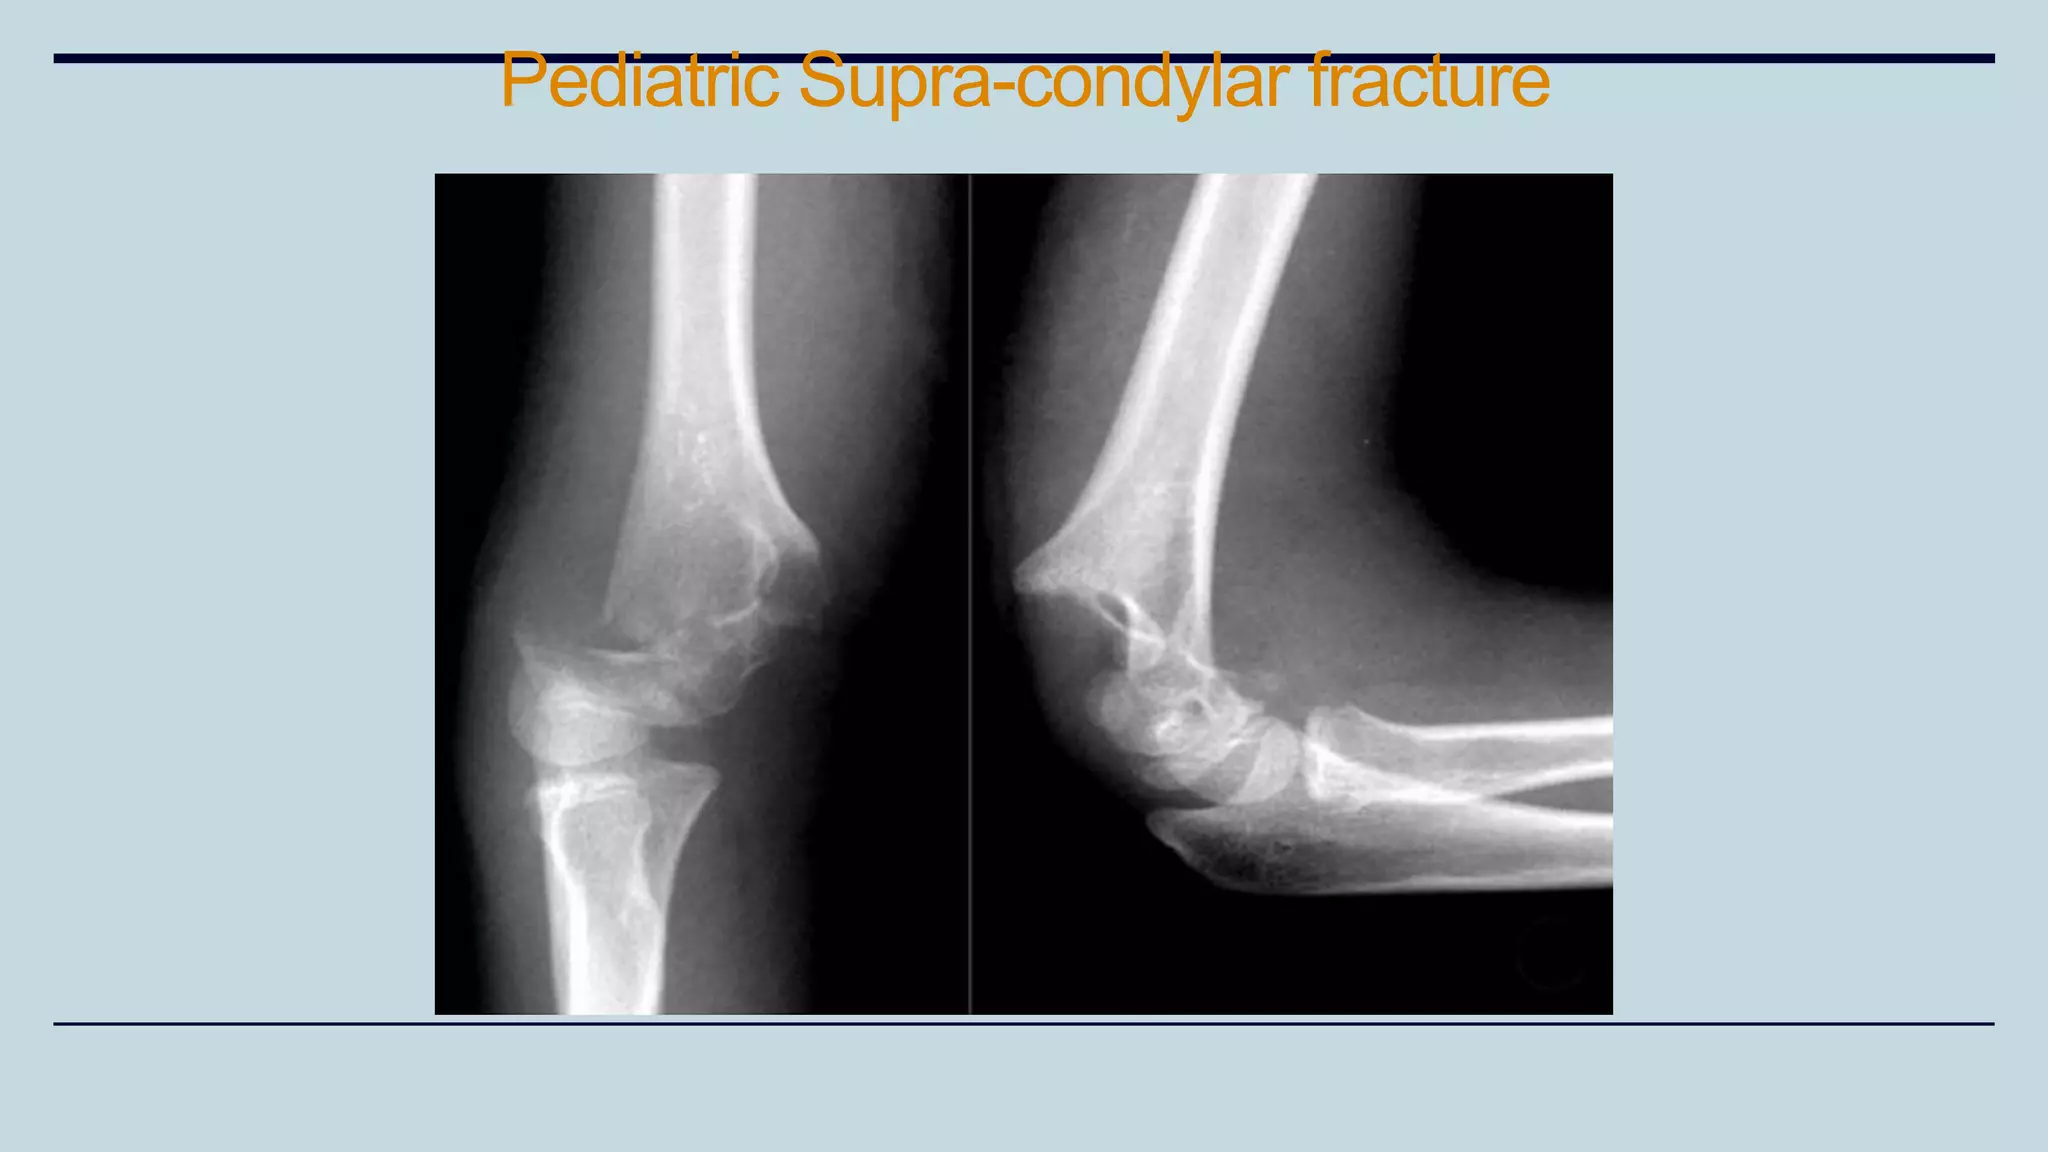

Supra- condylar Fracture of

Humerus

Types

It depends upon the displacement of the distal fragment.

• Extension type (80%)

• Flexion type (20%)

Presentation

• Pain, swelling, deformity and inability to move the affected elbow.

• Unusual posterior prominence of the elbow because of backward tilt of

distal fragment.

• 3 bony points relationship is maintained.

Pediatric Supra-condylar fracture